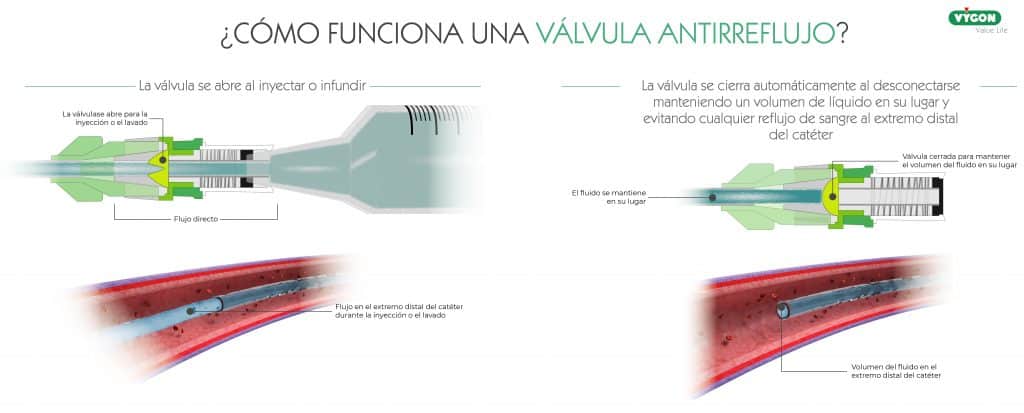

Las válvulas antirreflujo son dispositivos de desplazamiento neutro a los que se les ha añadido una válvula antirreflujo.

Se trata de una válvula de control del fluido bidireccional, la cual permanece cerrada hasta que la fuerza de infusión o extracción alcanza una presión especifica y, a medida que la presión de infusión o extracción empieza a reducirse, la válvula vuelve a cerrarse. De esta forma:

- Cuando la fuerza de infusión o extracción alcanza una presión especifica: la válvula se abre.

- Al detectar una caída de presión desde la bolsa de perfusión: la válvula se mantiene cerrada.

- Cuando se produce un aumento de la presión intratorácica: la válvula se mantiene cerrada.

- Al desconectar el Luer: la válvula se mantiene cerrada.

Actualmente, el conector antirreflujo es el único dispositivo que evita la entrada de sangre en el catéter en todas estas circunstancias. Se trata de la mejor forma de prevenir el reflujo sanguíneo y la aparición de oclusión, no obstante, es importante compararentre fabricantes ya que no todos ofrecen las mismas tasas de éxito.9

Las válvulas antirreflujo consiguen eliminar problemas de obstrucción en un 93,6% de los casos.10